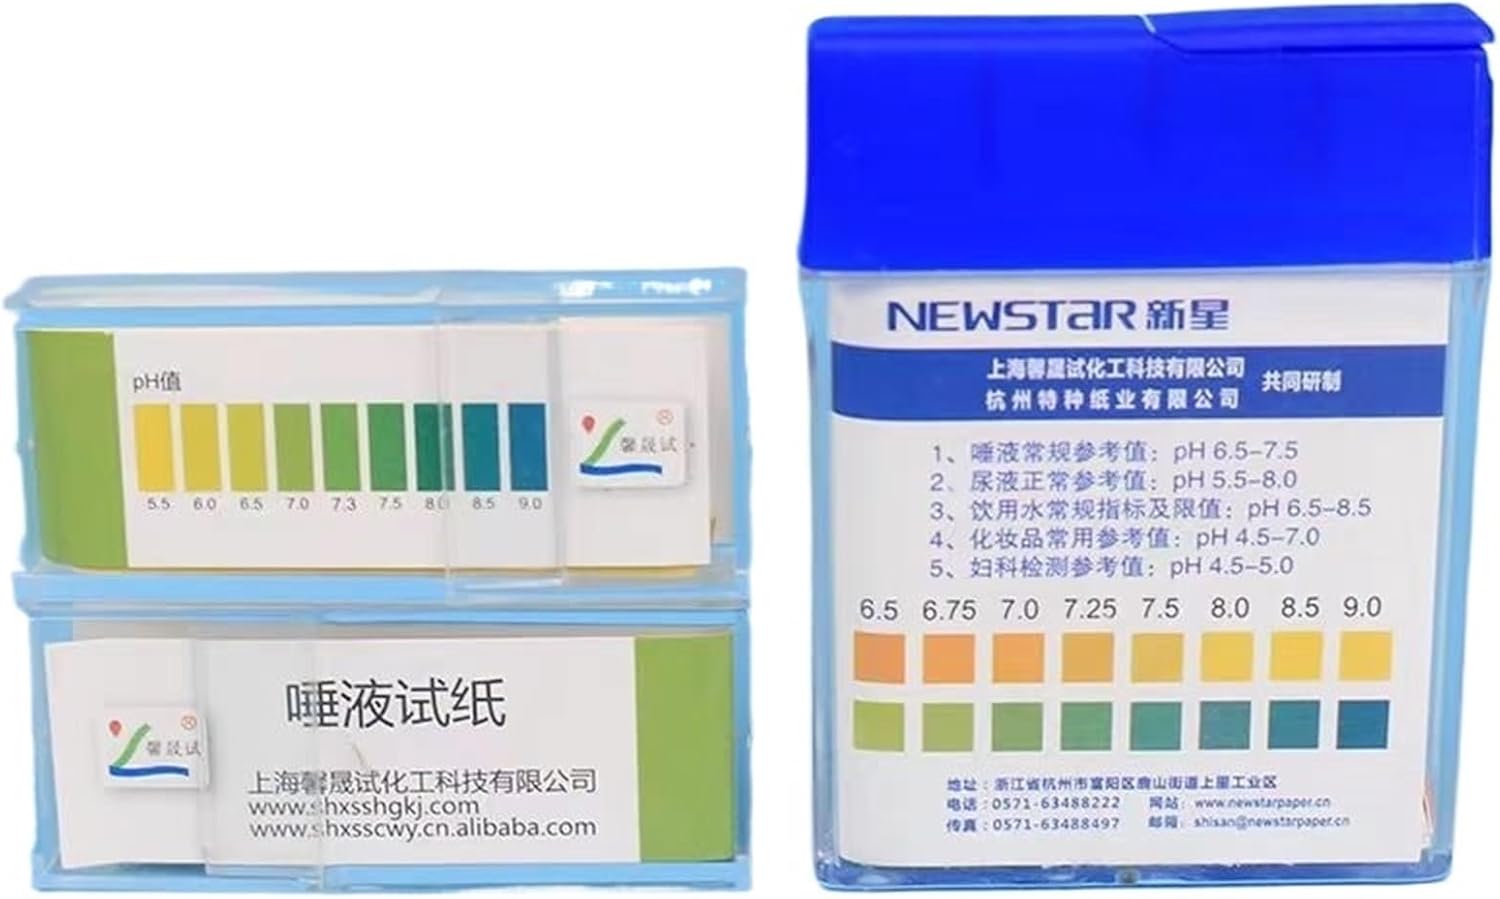

medical device

medical device